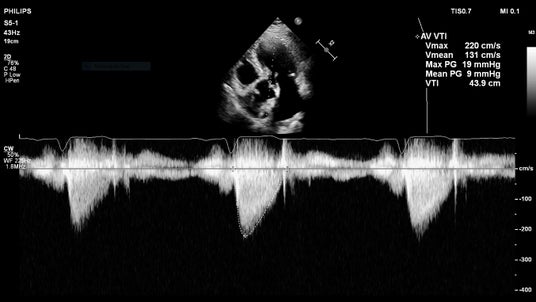

1. 自動計測機能の搭載「Auto Measure」と「AutoStrain LV」

据え置き型超音波診断装置EPIQ/Affinitiに搭載されていた循環器の自動計測や解析機能がCompact 5000 シリーズ2.0に搭載されました。Auto Measureはルーチンで計測されている多くの項目をAI技術により自動化しており、マニュアルでの計測と比較して最大51%の時間短縮が可能であることが報告されています[1]。 また、「AutoStrain LV」は左室ストレイン解析をワンボタンで実施するほかに、Simpson’s法による駆出率(EF)の自動算出にも対応しています。これらの自動化機能により、ポータブルでありながら迅速で効率的な検査の実施に貢献します。